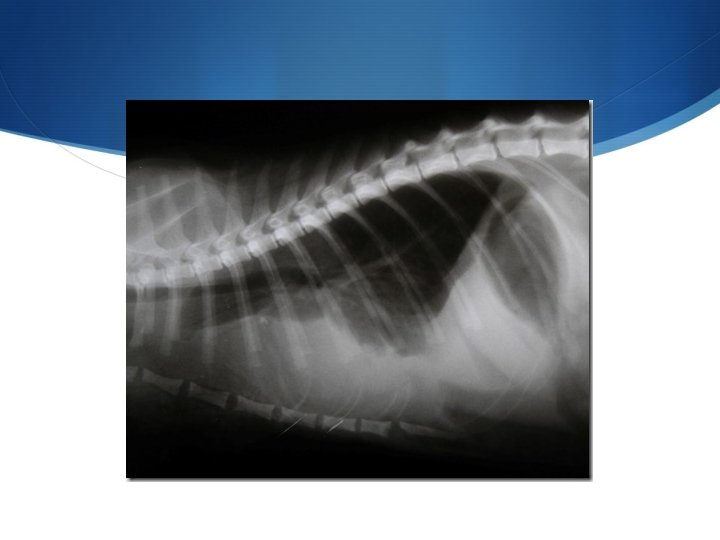

DIAGNOSI S ANAMNESI S Clinica. La palpazione della trachea nel suo tratto cervicale a volte può consentire il rilievo di FLACCIDITA’ TRACHEALE S RADIOGRAFIA (proiezione latero laterale) S ENDOSCOPIA S TAC

DIAGNOSI S CLINICA (ispezione, palpazione, auscultazione) S RX (IMPORTANZA DELLE PROIEZIONI) (RX PRIMA E DOPO TORACOCENTESI) S ECOGRAFIA S IMPORTANTE DETERMINARE L’EZIOLOGIA